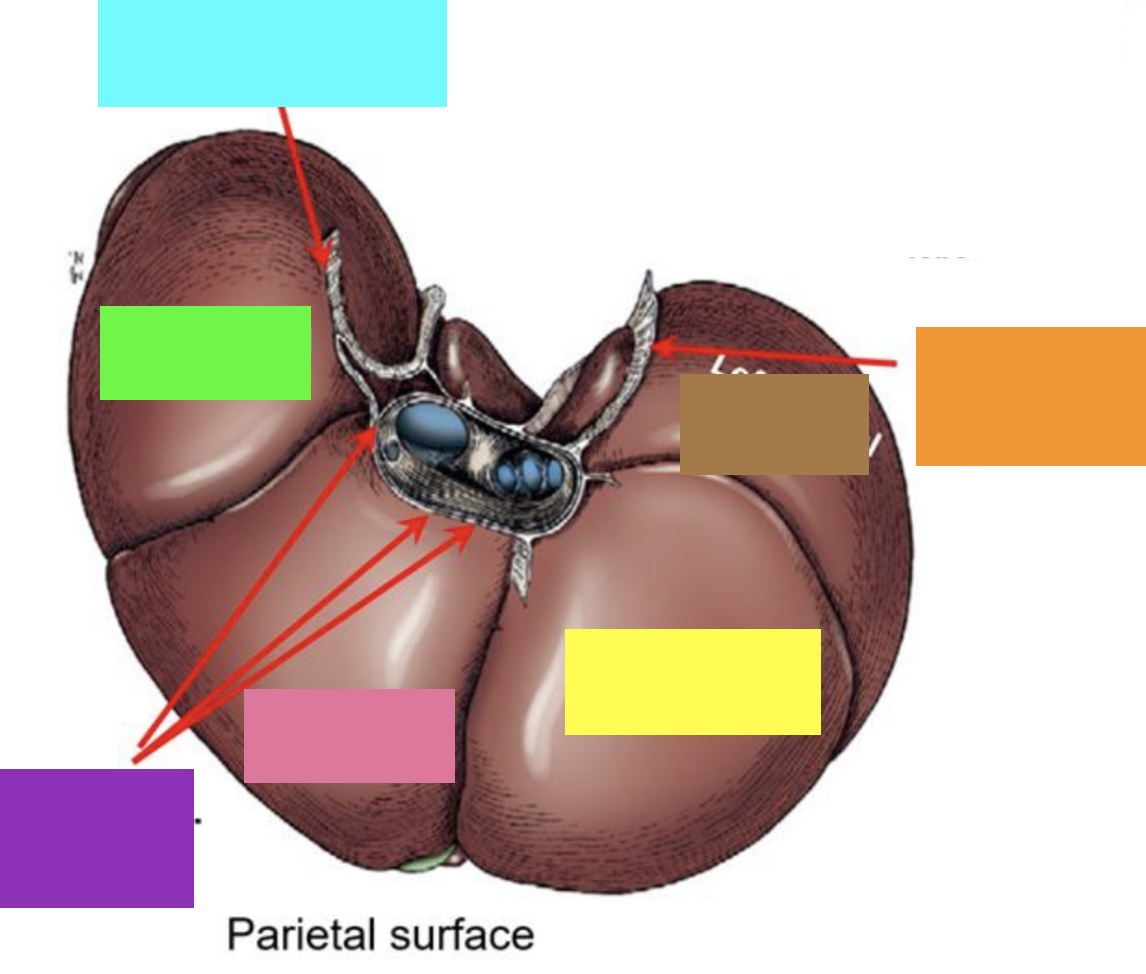

blue box

right triangular ligament

green box

right lateral lobe

purple box

coronary ligament

pink box

right medial lobe

yellow box

left medial lobe

orange box

left triangular ligament

brown box

left lateral lobe